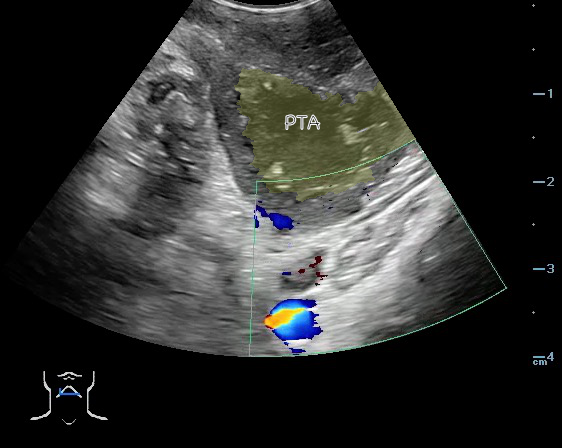

- The carotid artery is seen as an anechoic tubular structure along the posterolateral aspect of the tonsil on ultrasound. Its relationship to the abscess cavity should be determined. Color Doppler can help locate the carotid artery.

- Figure 47 and 48. PTA with color Doppler of carotid artery